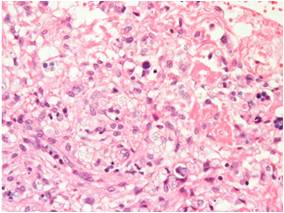

■ Examples of applications

Fluorescence in-situ hybridization (FISH) of an endothel cell.